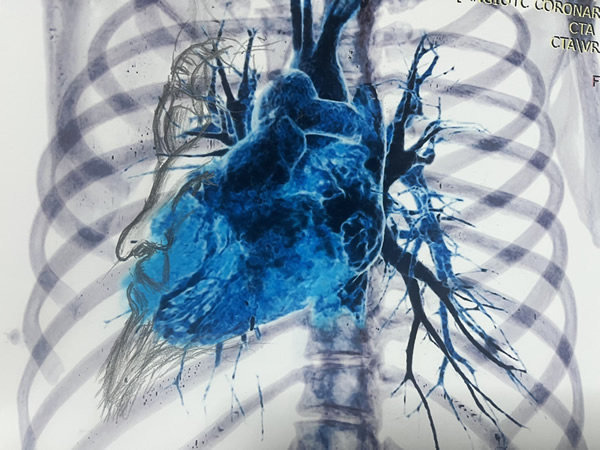

Patología aneurismática de cayado aórtico y aorta descendente torácica en paciente con dolor precordial atípico